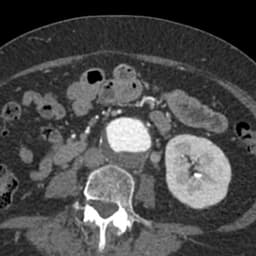

Upload one CTA, unlock the whole armamentarium. Amplifier AI auto-segments the aorta, arch, carotids, splanchnic trunks, and iliacs, then suggests exact graft sets for EVAR, TEVAR, or CERAB, complete with limb lengths and oversize margins.

Drop those devices or chimney grafts, carotid stents, renal or splenic coils - into a lifelike 3-D model and watch seal-zone heat-maps or flow simulations expose endoleak or embolic risk. For open thoraco-abdominal repair, rotate the aneurysm, pick clamp sites, and measure visceral re-implant cuffs. Trace micro-catheter runs for TACE or plot embolic angles for uncontrollable GI bleeds, all while colleagues observe remotely. The result is leaner inventory, shorter fluoroscopy, and a data-driven plan for every vascular scenario—from stroke prevention to life-saving haemostasis.